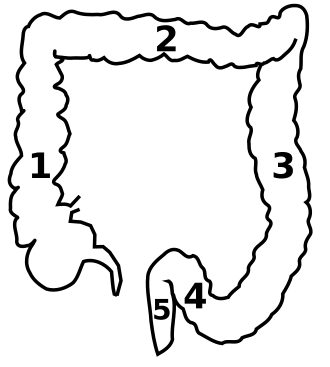

Der menschliche Dickdarm:

Beim Menschen verläuft das Colon ungefähr in Form eines umgedrehten U. Es werden fünf Abschnitte unterschieden:

- Caecum: Blinddarm (nicht zu verwechseln mit dem umgangssprachlich „Blinddarm“ genannten Wurmfortsatz)

- Colon ascendens: aufsteigendes Colon

- Colon transversum: Querkolon (Querdickdarm), nach der rechten Colonflexur (Flexura coli dextra)

- Colon descendens: absteigendes Colon, nach der linken Colonflexur (Flexura coli sinistra)

- Colon sigmoideum: Sigma-Schlinge, Sigma, Sigmoid